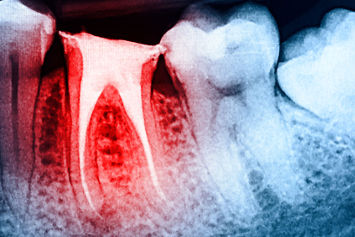

Celem leczenia jest całkowite oczyszczenie i dezynfekcja systemu kanałów korzeniowych na całej długości oraz szczelne ich wypełnienie. Przeprowadzamy je z reguły na jednej wizycie, co oszczędza czas i stanowi o komforcie leczenia. Bezbolesność zabiegu zapewniamy stosując znieczulenie komputerowe.

Trudność w wykonaniu całego leczenia kanałowego polega w głównej mierze na utrudnionym dostępie do bardzo małego pola zabiegowego rzędu 1 mm2 oraz konieczności opracowania wąskich, długich i krętych kanałów. Niezbędne w tej sytuacji jest długoletnie doświadczenie lekarza endodonty przeprowadzającego zabieg oraz nawet 40-to krotne powiększenie pola zabiegowego. Powiększenie to uzyskujemy stosując najnowocześniejszy mikroskop zabiegowy. Nawet w trudnych warunkach anatomicznych wgląd we wnętrze zęba pozwala na całkowite udrożnienie kanałów, co jest gwarantem wycofania się okołowierzchołkowych procesów zapalnych. Optyka mikroskopowa warunkuje małoinwazyjne i oszczędzające korzeń zęba usunięcie złamanych, pozostawionych w kanałach narzędzi. Skuteczność zabiegu wymaga pełnej dezynfekcji systemu kanałów korzeniowych oraz szczelnego ich wypełnienia. System ciekłej gutaperki stosowany w naszej klinice od wielu lat to sprawdzona metoda szczelnego i niezawodnego wypełniania kanałów korzeniowych.

Każdy etap pracy weryfikujemy wykonując cyfrową radiowizjografię RVG a w razie konieczności odcinkową tomografię komputerową CBCT.